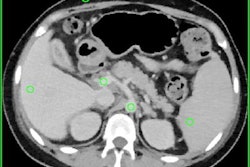

Rather than acquire images in a single broad energy band, as does conventional CT, spectral CT separates energy into two or more narrow energy bands. Because different types of energies are absorbed differently by tissues, they can provide insights into the different chemical compositions of tissues.

Conventional CT scanners can only perform spectral CT with two separate scans, each at different energy levels. There are inherent problems with such an approach, however, so vendors have introduced new techniques and scanners designed to enable spectral CT to be performed in one scan, according to ECRI.

The report noted that despite 10 years of availability, spectral CT does not yet have a solid foundation of evidence demonstrating its clinical benefits. But it is being touted as a good tool for improved soft-tissue contrast and tissue characterization.